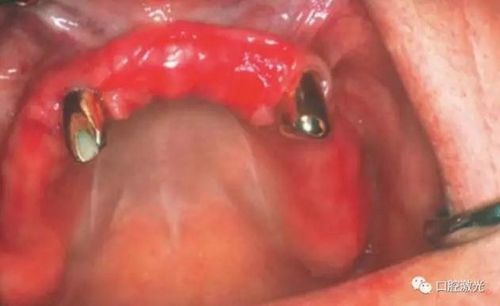

對(duì)患者實(shí)施局部麻醉,隨后在種植體位置進(jìn)行翻瓣。利用塑料刮治器將肉芽組織清除干凈,并將翻瓣邊緣削薄。此時(shí)在種植體周圍可見(jiàn)明顯骨缺失。

利用半導(dǎo)體激光照射已經(jīng)暴露的種植體表面。激光輸出功率1.0W,連續(xù)模式,照射時(shí)間20秒,光纖芯徑400um,光纖尖不初始化。由于激光的選擇性吸收的特點(diǎn),該激光能量設(shè)定足以殺滅導(dǎo)致種植體周圍炎的厭氧菌,卻不會(huì)對(duì)種植體表面和種植體周圍生物組織(骨組織、黏膜組織)造成熱或者機(jī)械損害。在軟組織恢復(fù)6周和12周后分別再進(jìn)行一次激光滅菌治療(參照牙周炎激光滅菌程序)。